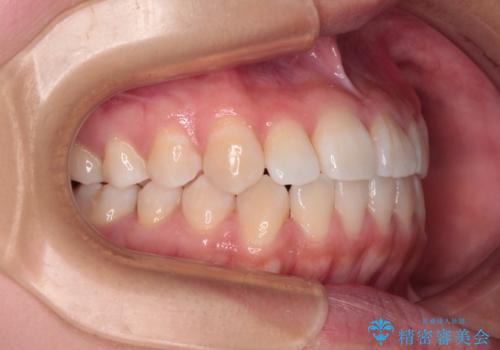

- 前歯のデコボコを治したいとのことで来院された患者様です。

インビザラインによるマウスピース矯正も適用となる歯列でしたが、できる限り楽して、短期間で治したいとのことで、ワイヤー装置にて矯正治療を行うこととしました。